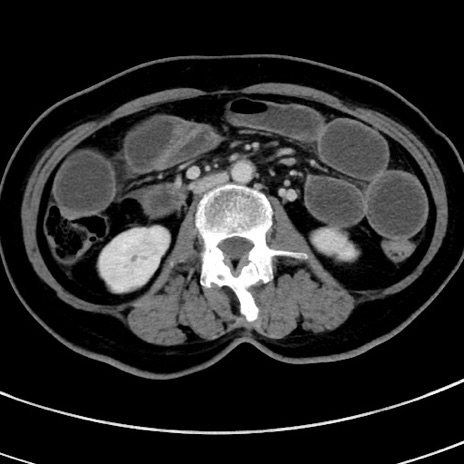

症例9(横断像)

【症例】 60歳代女性

【主訴】むかつき、みぞおちの痛み

【現病歴】3日前よりむかつきがあり、食事がとれない。

【既往歴】糖尿病

【身体所見】発熱なし、心窩部圧痛軽度あるも、腹膜刺激症状なし。

【データ】WBC 7400、CRP 1.92